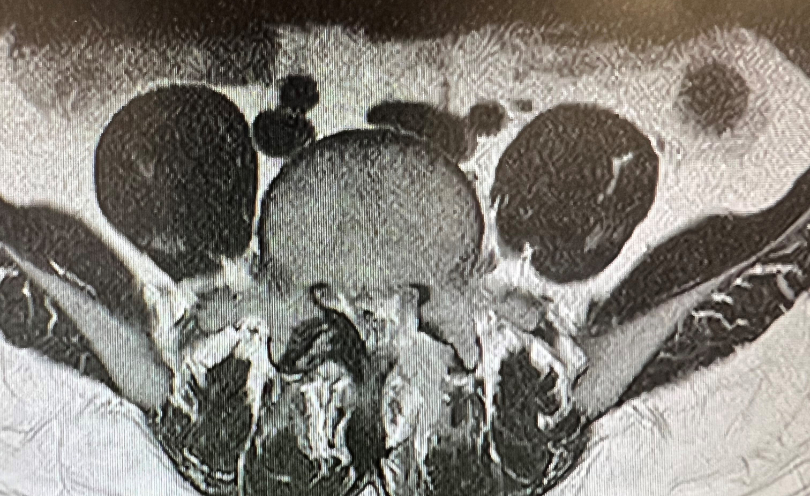

患者术前影像检查资料

患者就诊后,影像学检查显示腰4-5和腰5骶1两个节段均存在突出。其中腰4-5椎间盘突巨大突出,双侧神经根受压。

术后复查核磁

术后当天,患者术前下肢疼痛麻木症状缓解,无其他不适,复查核磁硬膜囊膨隆,减压效果满意。